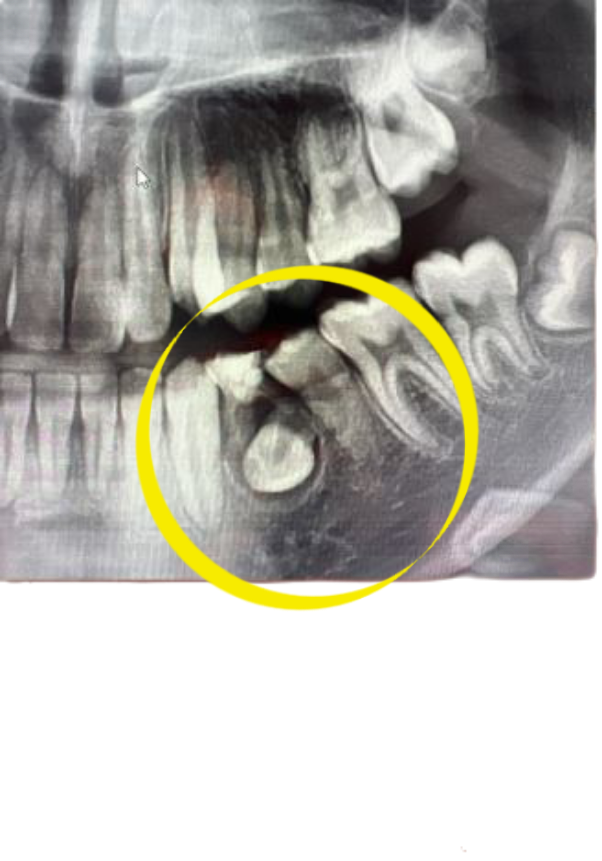

사진으로 봤을 경유 영구치의 맹출방향이 잘못되어 정상적인 맹출이 되지 않고 있는것으로 보입니다.

유치가 잔존해있으나 하방의 계승 영구치의 낭성 병소로인해 뿌리는 녹아있는 상태입니다

영구치에 대해서는 좀 더 평가를 해봐야하지만 해당 부위 유치, 영구치 모두 못쓸 수도 있습니다

만약 하방 영구치의 치관(치아머리)주위가 낭포가 형성된 것이 맞다고 병리학적으로 판단되면 수술을 통해 낭을 적출합니다 물혹을 제거하는 수술이라고 보시면 됩니다

그 후에 뼈가 다시 차오르는것도 지켜보고 턱 성장도 끝난 18세 이후로 해당 부위 임플란트 식립을 고려해봐야합니다 그 전까지는 공간유지장치 겸 임시틀니를 하고 있을 수 있습니다

이건 해당부위 영구치를 못쓰는 경우 그렇고 쓸 수 있는 상태면 교정 및 수술 통해 끌어올려 제자리에 위치시켜 사용합니다

또한 해당 사진은 ct가 아니고 파노라마 방사선사진입니다

치료및 진단에 필요하다면 ct사진을 찍어야할수도 있습니다